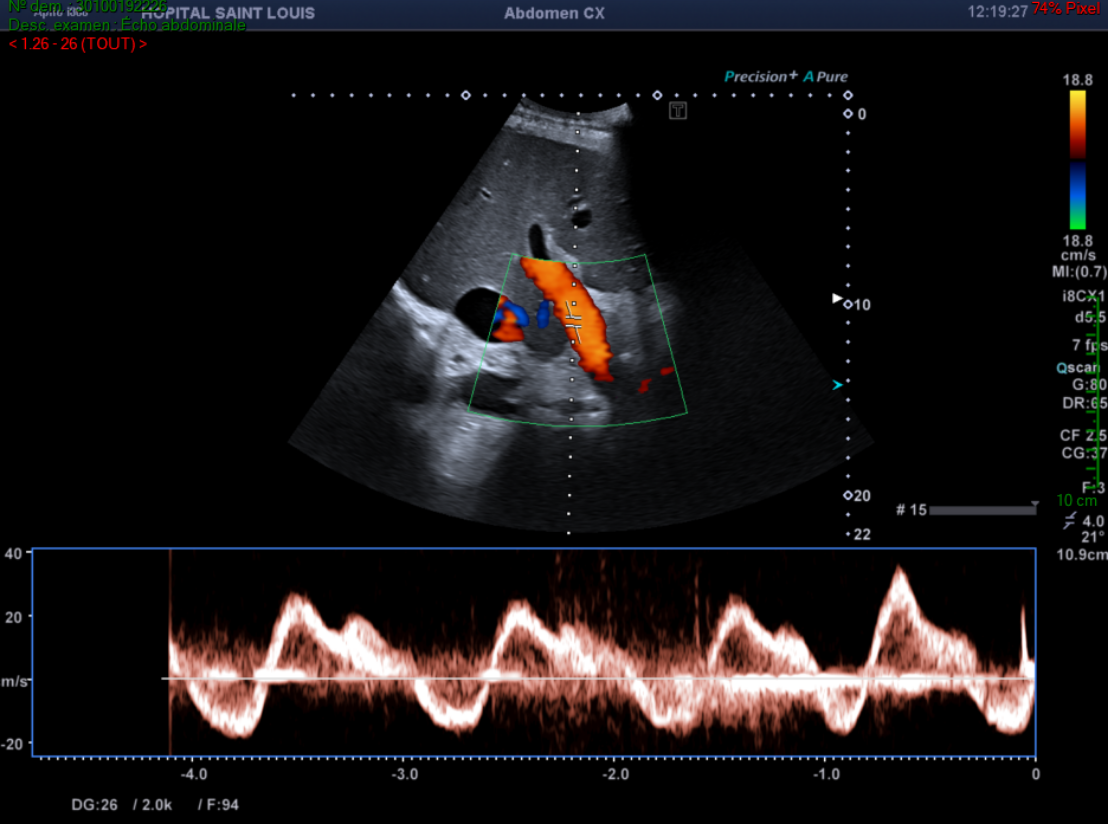

De plus, le flux du tronc porte attire son attention.

Il observe alors une alternance entre un flux hépatopète et hépatofuge au sein du tronc porte.

Un flux portal normal est dirigé vers le foie (hépatopète).

Un spectre normal du tronc porte est continu avec une légère pulsatilité liée à la décélération lors de l’inspiration.

Une importante pulsatilité est évocatrice d’une dysfonction ventriculaire droite et/ou d’une importante insuffisance tricuspide, signe indirect d’une hypertension artérielle pulmonaire.

Pulsatilité du tronc porte